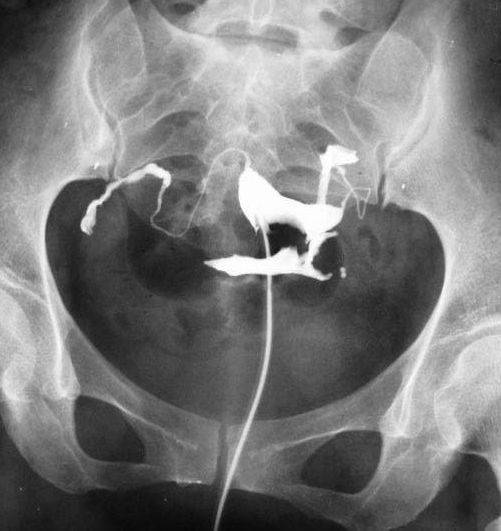

子宮輸卵管造影X線圖:醫(yī)學(xué)|教育網(wǎng)整理